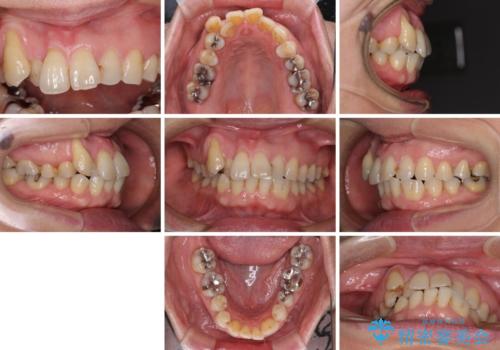

- 長年前歯の歯並びで悩んでいるとのことで来院された患者様です。

機能的なことを考えると八重歯となっている犬歯は抜歯せず、歯列を改善することが望ましいとされますが、数十年もの間犬歯がない咬み合わせで問題なく過ごしてきたため、八重歯を抜歯することで、手っ取り早く歯列を改善することとしました。

また、当初は予定しておりませんでしたが、歯列が整ったことで前歯の歯の色や形が気になり、矯正治療後にオールセラミッククラウンにて補綴治療することとしました。